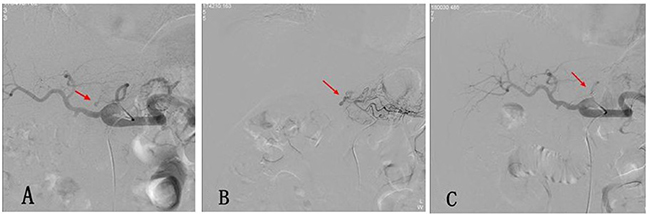

All DSA procedures were technically successful, and initial hemostasis was achieved in 29 patients. Of the 29 patients, pseudoaneurysm alone was observed in one patient (3.4%), pseudoaneurysm and active extravasation in two (6.9%), active extravasation in 22 (75.9%), and luminal irregularity in four (13.8%). The hemorrhagic focus in the angiograms was observed in the gastroduodenal artery (GDA) stump in 11 patients, in the hepatic artery in 13, in the superior mesenteric artery in two, in the left gastric artery in two (Figure 2), and in the splenic artery in one. A pushable coil (selective artery embolization) was used as the embolizing agent in 15 patients, and a covered stent was used for one patient (Figure 1). Embolization was established with a pushable coil along with PVA in three cases, a pushable coil along with a gelatin sponge particle in five cases, and a gelatin sponge particle alone in five cases. Recurrent bleeding occurred in eight of the 29 patients (27.6%) after the first endovascular treatment. A repeat procedure was performed in five patients, though the bleeding sites were not discovered, and three patients underwent a laparotomy following endovascular procedures for a washout of a massive hemoperitoneum performed at the discretion of the surgical team (Table 2). Five of the 13 patients with a negative DSA examination changed to symptomatic supportive treatment, and the other eight patients were evaluated using an endoscopy (n = 4, 1 with capsule endoscopy) and a laparotomy (n = 4) to identify the source of hemorrhage. No procedure-related complication developed in any other case. No rebleeding in a late stage occurred in the other cases. Mortality occurred in five (17.2 %) of the 29 patients: two died from severe infections and three from multiple organ failure.

Figure 2: (A) Postoperative hemorrhage after Whipple operation. The selective celiac artery arteriography shows the overflow of the contrast agent at the local left gastric artery (arrow). (B) The super-selective angiography of the left gastric artery with a 2.7 F micro-catheter shows the local overflow of the contrast agent (arrow). (C) A micro-spring steel ring was used for the embolization of the proximal end of the left gastric artery, and a re-examination using an angiography was performed, which revealed signs that the contrast agent overflow disappeared.